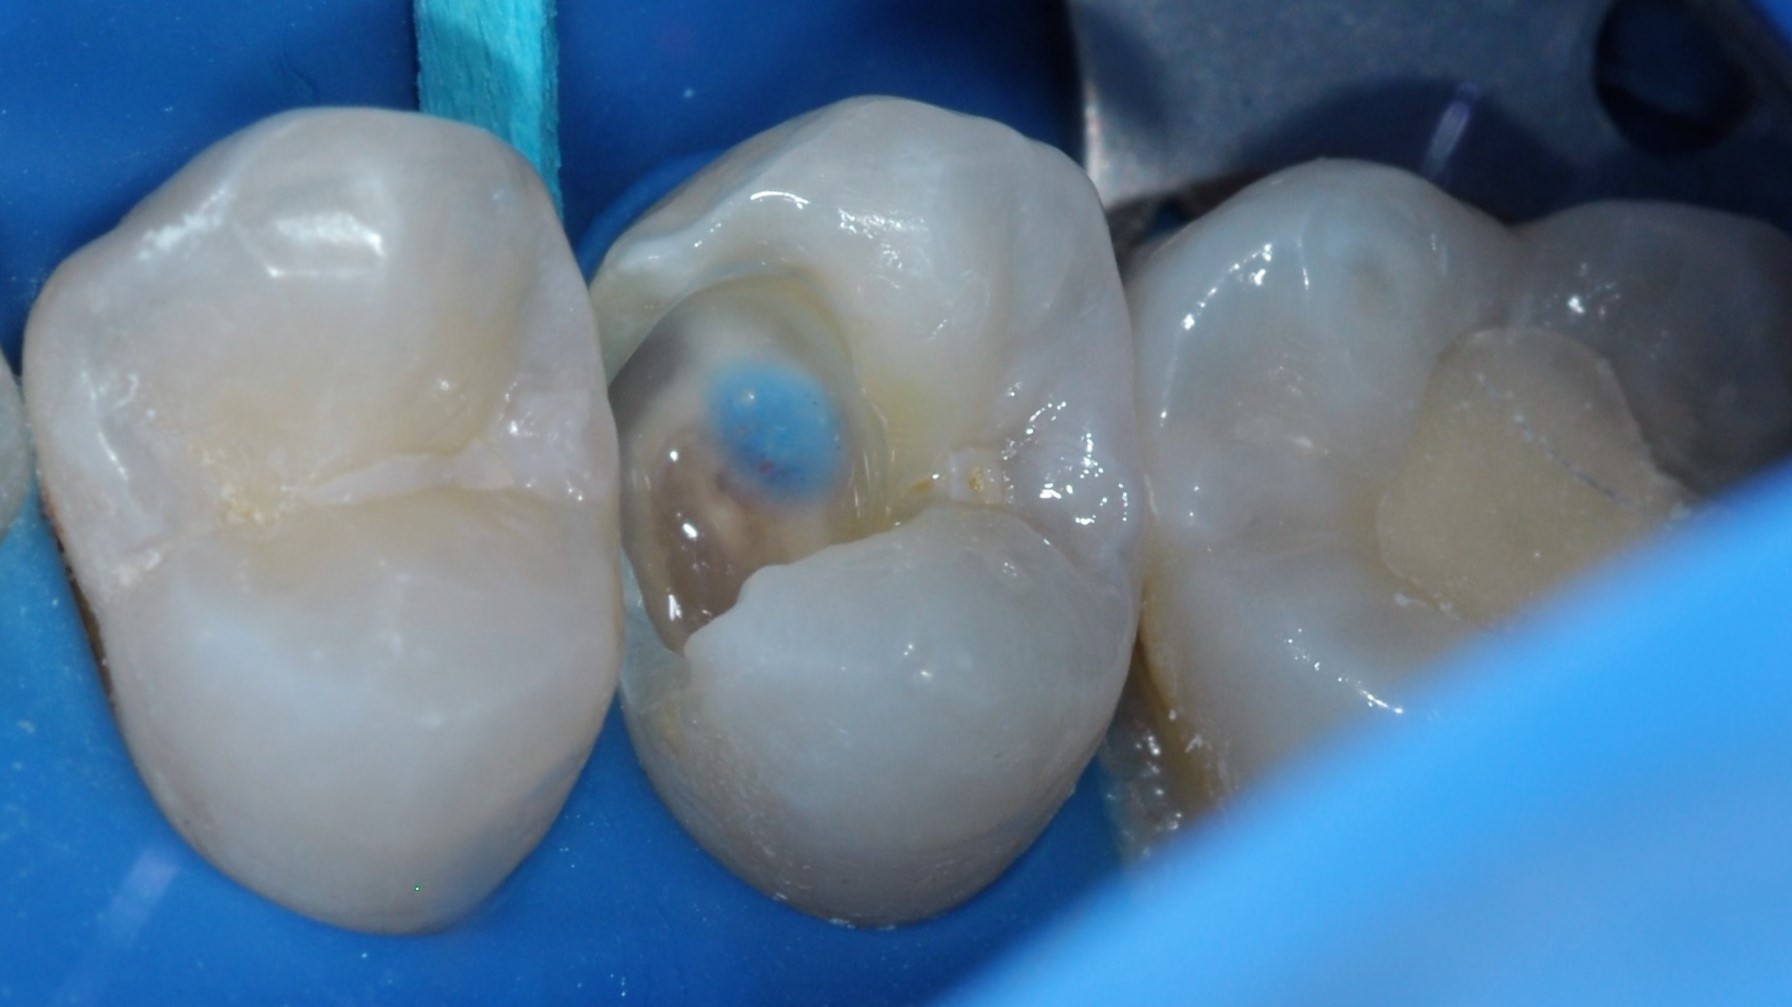

Leczenie zachowawcze zęba 15 rozpoczęto od testu żywotności (reakcja na bodziec zimny prawidłowa). Wykonano znieczulenie nasiękowe oraz izolację pola zabiegowego koferdamem (Rubber-Dam, Cerkamed) (ryc. 1). Ubytek opracowywano zgodnie z wytycznymi Europejskiego Towarzystwa Endodontycznego (European Society of Endodontology – ESE) w sprawie leczenia próchnicy głębokiej i obnażeń miazgi (1). W pierwszej kolejności, w powiększeniu, przy użyciu mikroskopu, wiertłem diamentowym na końcówce przyspieszającej usunięto próchnicowo zmienione szkliwo. Następnie wiertłem różyczkowym na mikrosilnik usunięto zainfekowaną bakteryjnie zębinę na peryferiach ubytku (infected dentine, soft dentine). Zbliżając się do komory zęba, zmieniono wiertło na sterylne i na niskich obrotach usuwano kolejne partie zębiny zainfekowanej. Podczas końcowej fazy opracowania ubytku doszło do próchnicowego obnażenia miazgi (obnażenie miazgi klasy II według ESE) (1) (ryc. 2). Zębinę zdemineralizowaną (affected dentine, firm dentine) pozostawiono w dnie ubytku. Krwawienie z miejsca obnażenia zahamowano sterylną gąbką, nasączoną roztworem 0,9-procentowym NaCl, uciskając przez 5 minut. Obnażenie zaopatrzono materiałem na bazie MTA (BIO MTA +, Cerkamed) i pozostawiono do wstępnego związania przez 12 minut (ryc. 3).

Ryc. 3. Przykrycie bezpośrednie (BIO MTA +, Cerkamed). Na ścianie dokomorowej widać firm dentine.

W celu zabezpieczenia biomateriału przed nadmiarem wilgoci zastosowano jednobuteleczkowy, samotrawiący, uniwersalny system wiążący Clearfil Universal Bond Quick (Kuraray Noritake) (ryc. 4). Prosta i szybka aplikacja oraz wysoka zawartość monomeru 10-MDP pozwala na trwałe, chemiczne wiązanie z wapniem w MTA oraz zębinie (2-4). Miejsce obnażenia pokryto płynnym materiałem kompozytowym w kolorze niebieskim (Color Flow, Cerkamed) (ryc. 5).

Ryc. 4. Aplikacja systemu wiążącego Clearfil Universal Bond Quick (Kuraray Noritake) na całą zębinę i materiału Color Flow (Cerkamed) na miejsce przykrycia miazgi.

Zaznaczenie miejsca obnażenia kolorowym materiałem flow ma zastosowanie dydaktyczne. W codziennej praktyce autorka nie wykonuje tej procedury. Podczas wyboru materiału odtwórczego ważniejsze znaczenie mają parametry wytrzymałościowe (na przykład zawartość napełniacza i presilanizacja cząstek napełniacza) (37). Na niekorzyść mocno napigmentowanych materiałów przemawia utrudniona penetracja promieni lampy polimeryzacyjnej oraz odbijanie niebieskiego światła przez materiał w kolorze niebieskim. Wzrost długości czasu polimeryzacji wiąże się z możliwością termicznego uszkodzenia miazgi (3, 4).